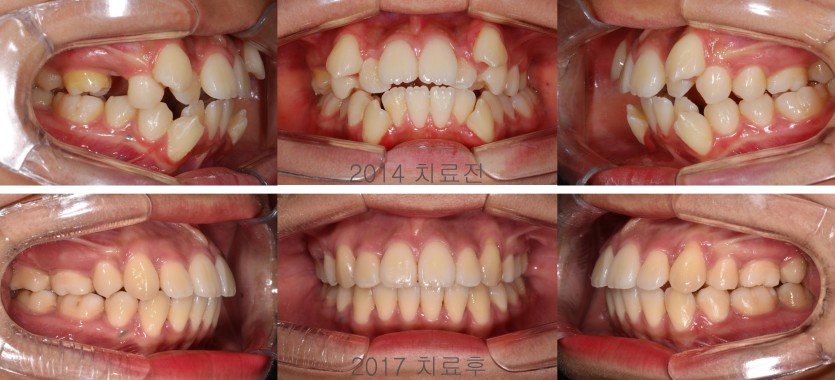

일반적인 덧니 상황에서는 소구치 발치교정치료만으로 상당한 배열공간을 확보할 수 있습니다. 그러나, 상하 대구치간 폭경이 조화롭지 않아 상악 치열을 확장하면서 소구치를 발치해야 하는 경우도 가끔 만납니다. 상악 치조골의 크기가 현저히 작기 때문입니다. 상악을 급속 확장장치로 확장하여 상악 대구치가 하악 대구치를 덮을 수 있도록 만들어주고 발치치아를 재진단하여 발치 교정치료를 진행합니다. 그 역순으로 발치를 먼저하고 후속적으로 대구치 확장을 하는 방법은 적절하지 않습니다. 치료의 순서를 정확히 지키면서 치료해야 합니다.